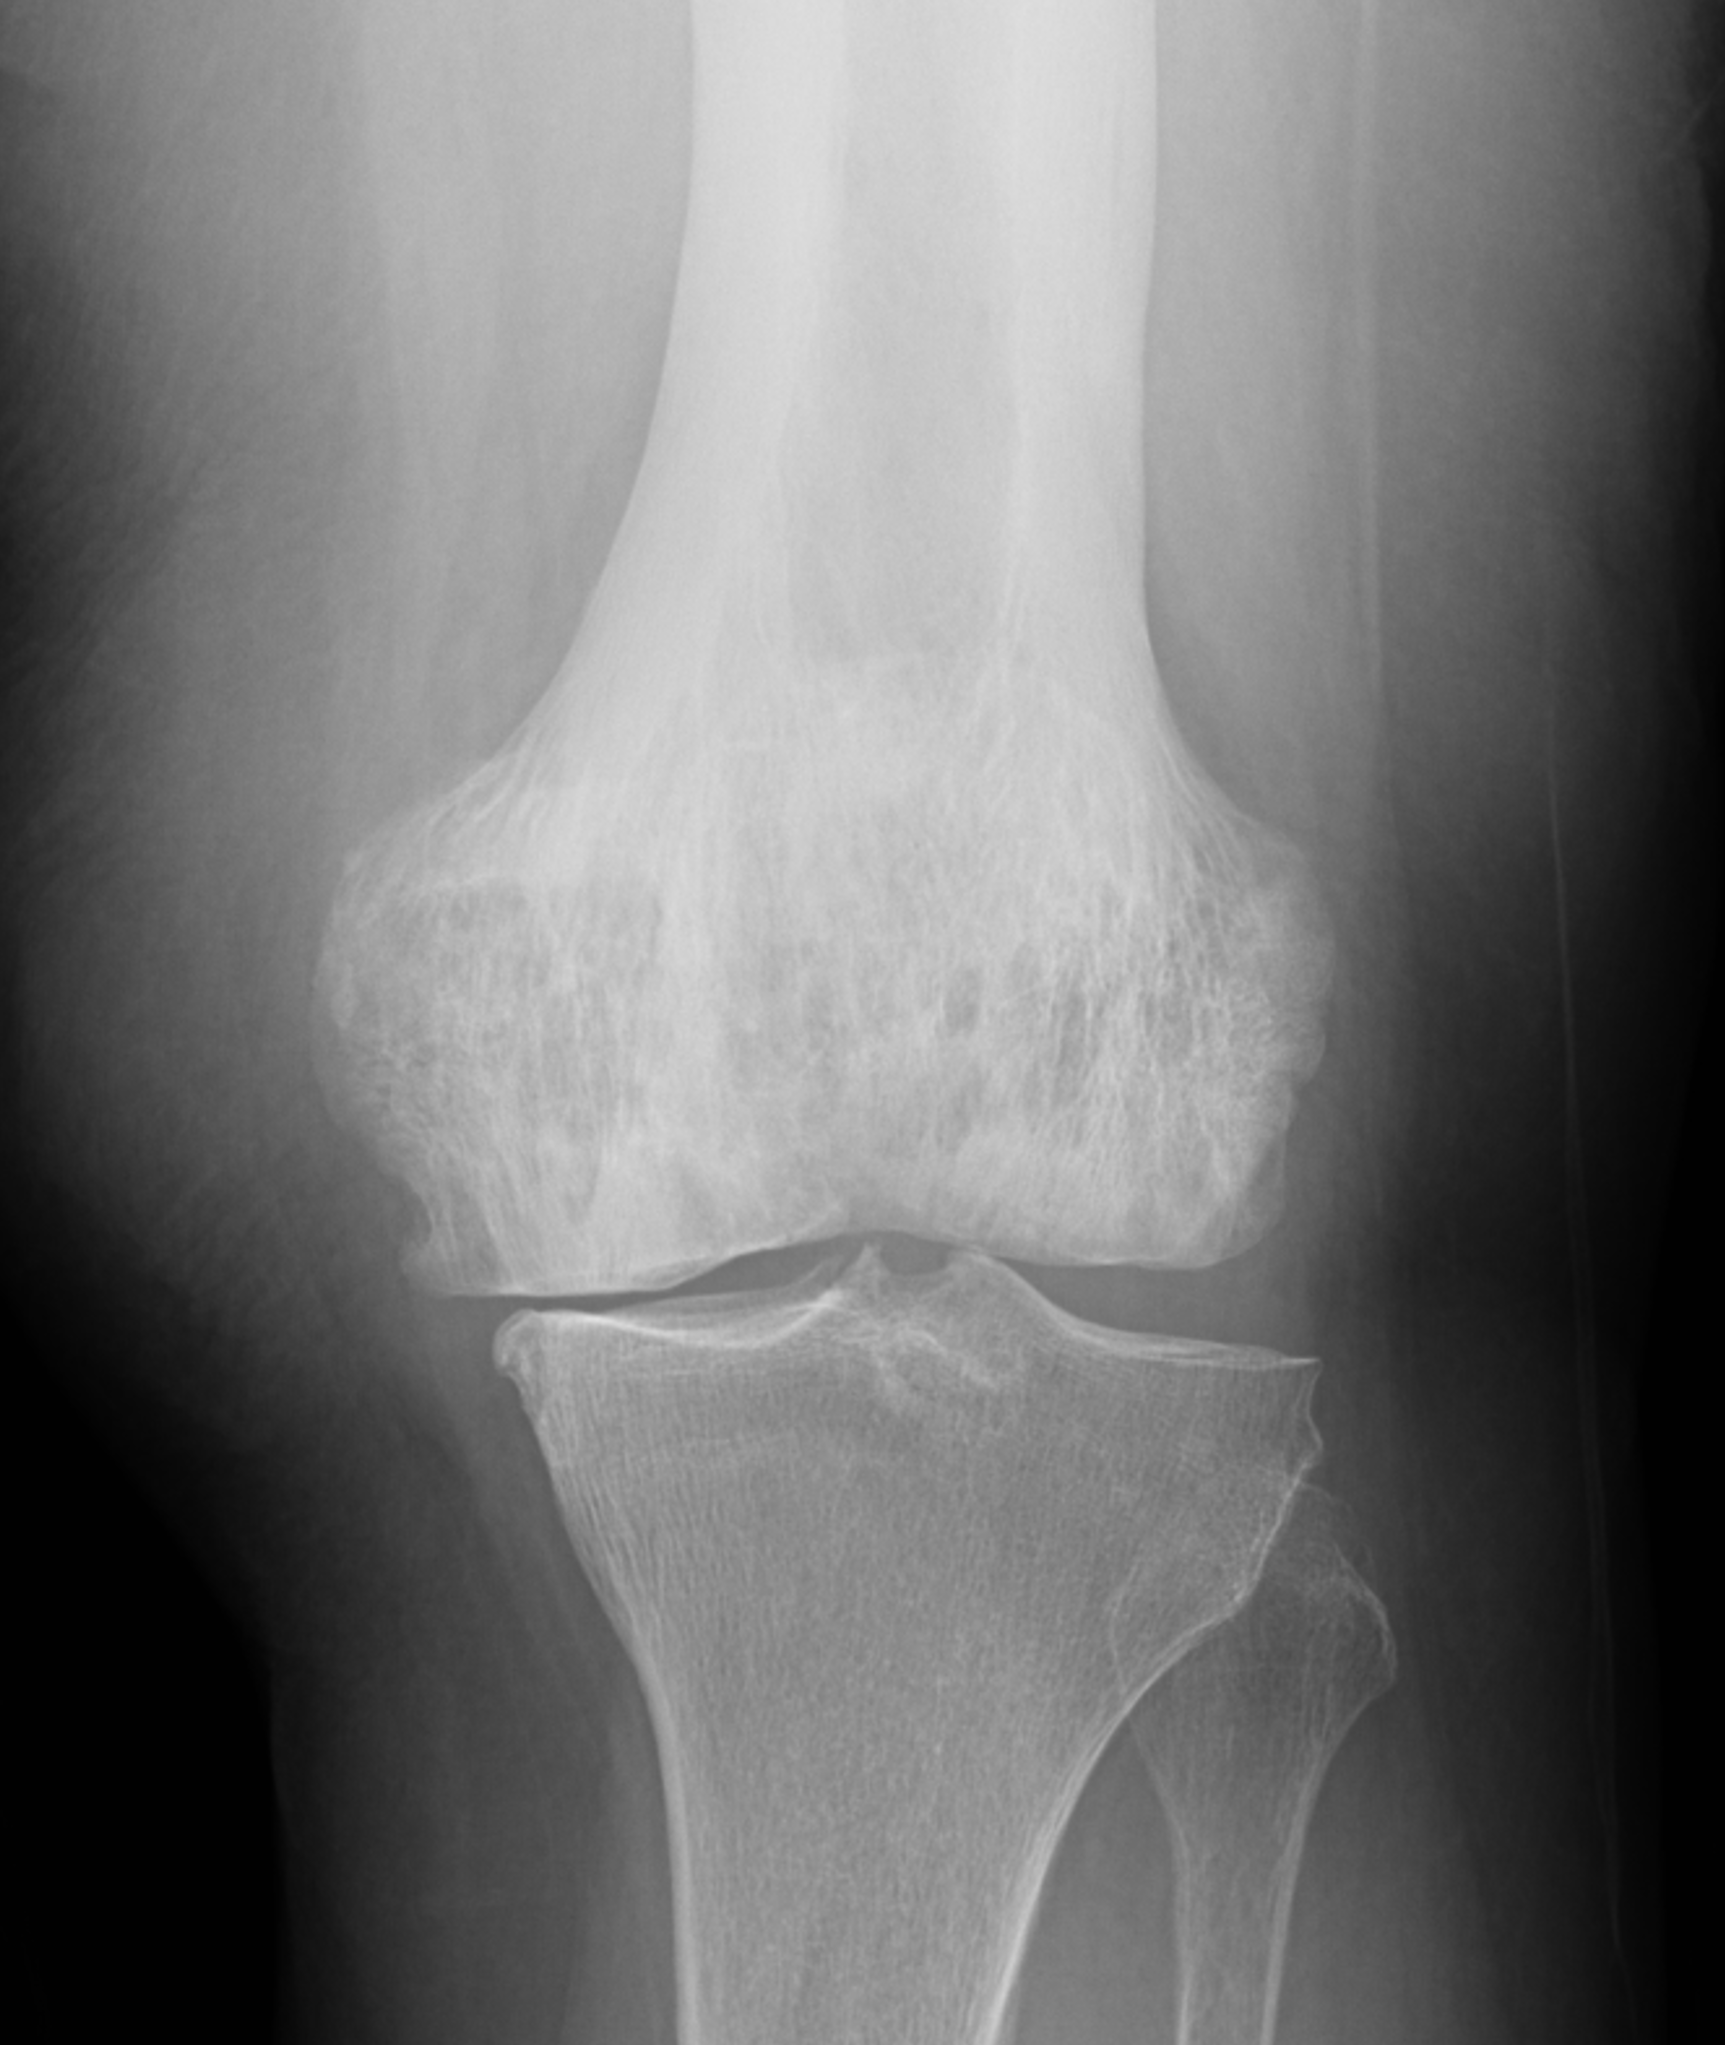

An elderly man presents with generalized knee pain. A sagittal T1-weighted image (1A) of the knee, axial fat-suppressed, fluid sensitive images through the distal femoral shaft (1B) and femoral condyles (1C), and an AP radiograph (1D) of the knee are provided. What are the findings? What is your diagnosis?

Figure 2: (2A) Sagittal T1-weighted image shows severe thickening of the distal femoral cortex (yellow arrow) and thickening and coarsening of the trabeculae in the femoral condyles (red arrow). Note the high signal intensity fatty marrow in both regions. (2B) Axial fat-suppressed, fluid sensitive sequence through the distal femoral shaft shows severe thickening of the bone cortex, with small round and tubular high-signal intensity foci within the cortex (arrow), likely representing cysts and dilated vascular spaces. (2C) Axial fat-suppressed, fluid sensitive sequence through the femoral epicondyles shows heterogeneous marrow (asterisks), with areas of suppressed marrow fat, mildly increased marrow signal intensity, and small cyst-like lesions. (2D) AP radiograph shows typical findings of mixed phase Paget disease in the distal femur including cortical thickening, course trabeculae, and bone enlargement. Secondary medial compartment predominant osteoarthritis has developed, likely contributing to symptoms.